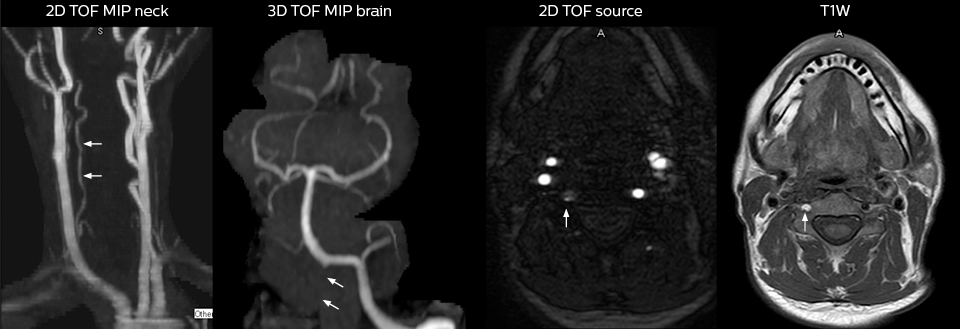

Für Dr. Karis bestehen die nächsten Ziele für die neurologische Notaufnahme in der Umstellung der Untersuchungen für akute Schlaganfall- und TIA-Patienten von CT auf MRT, was eine alternative Managementoption für diese Patienten darstellt. Außerdem wird derzeit die Kooperation mit anderen Abteilungen in die Wege geleitet, was den Nutzen zielgerichteter Untersuchungen mit dem MRT-System in der Notaufnahme noch erhöht. Diese Verbesserungen im Arbeitsablauf können in Kombination mit kürzeren Durchlaufzeiten die Untersuchungsdauer weiter reduzieren.